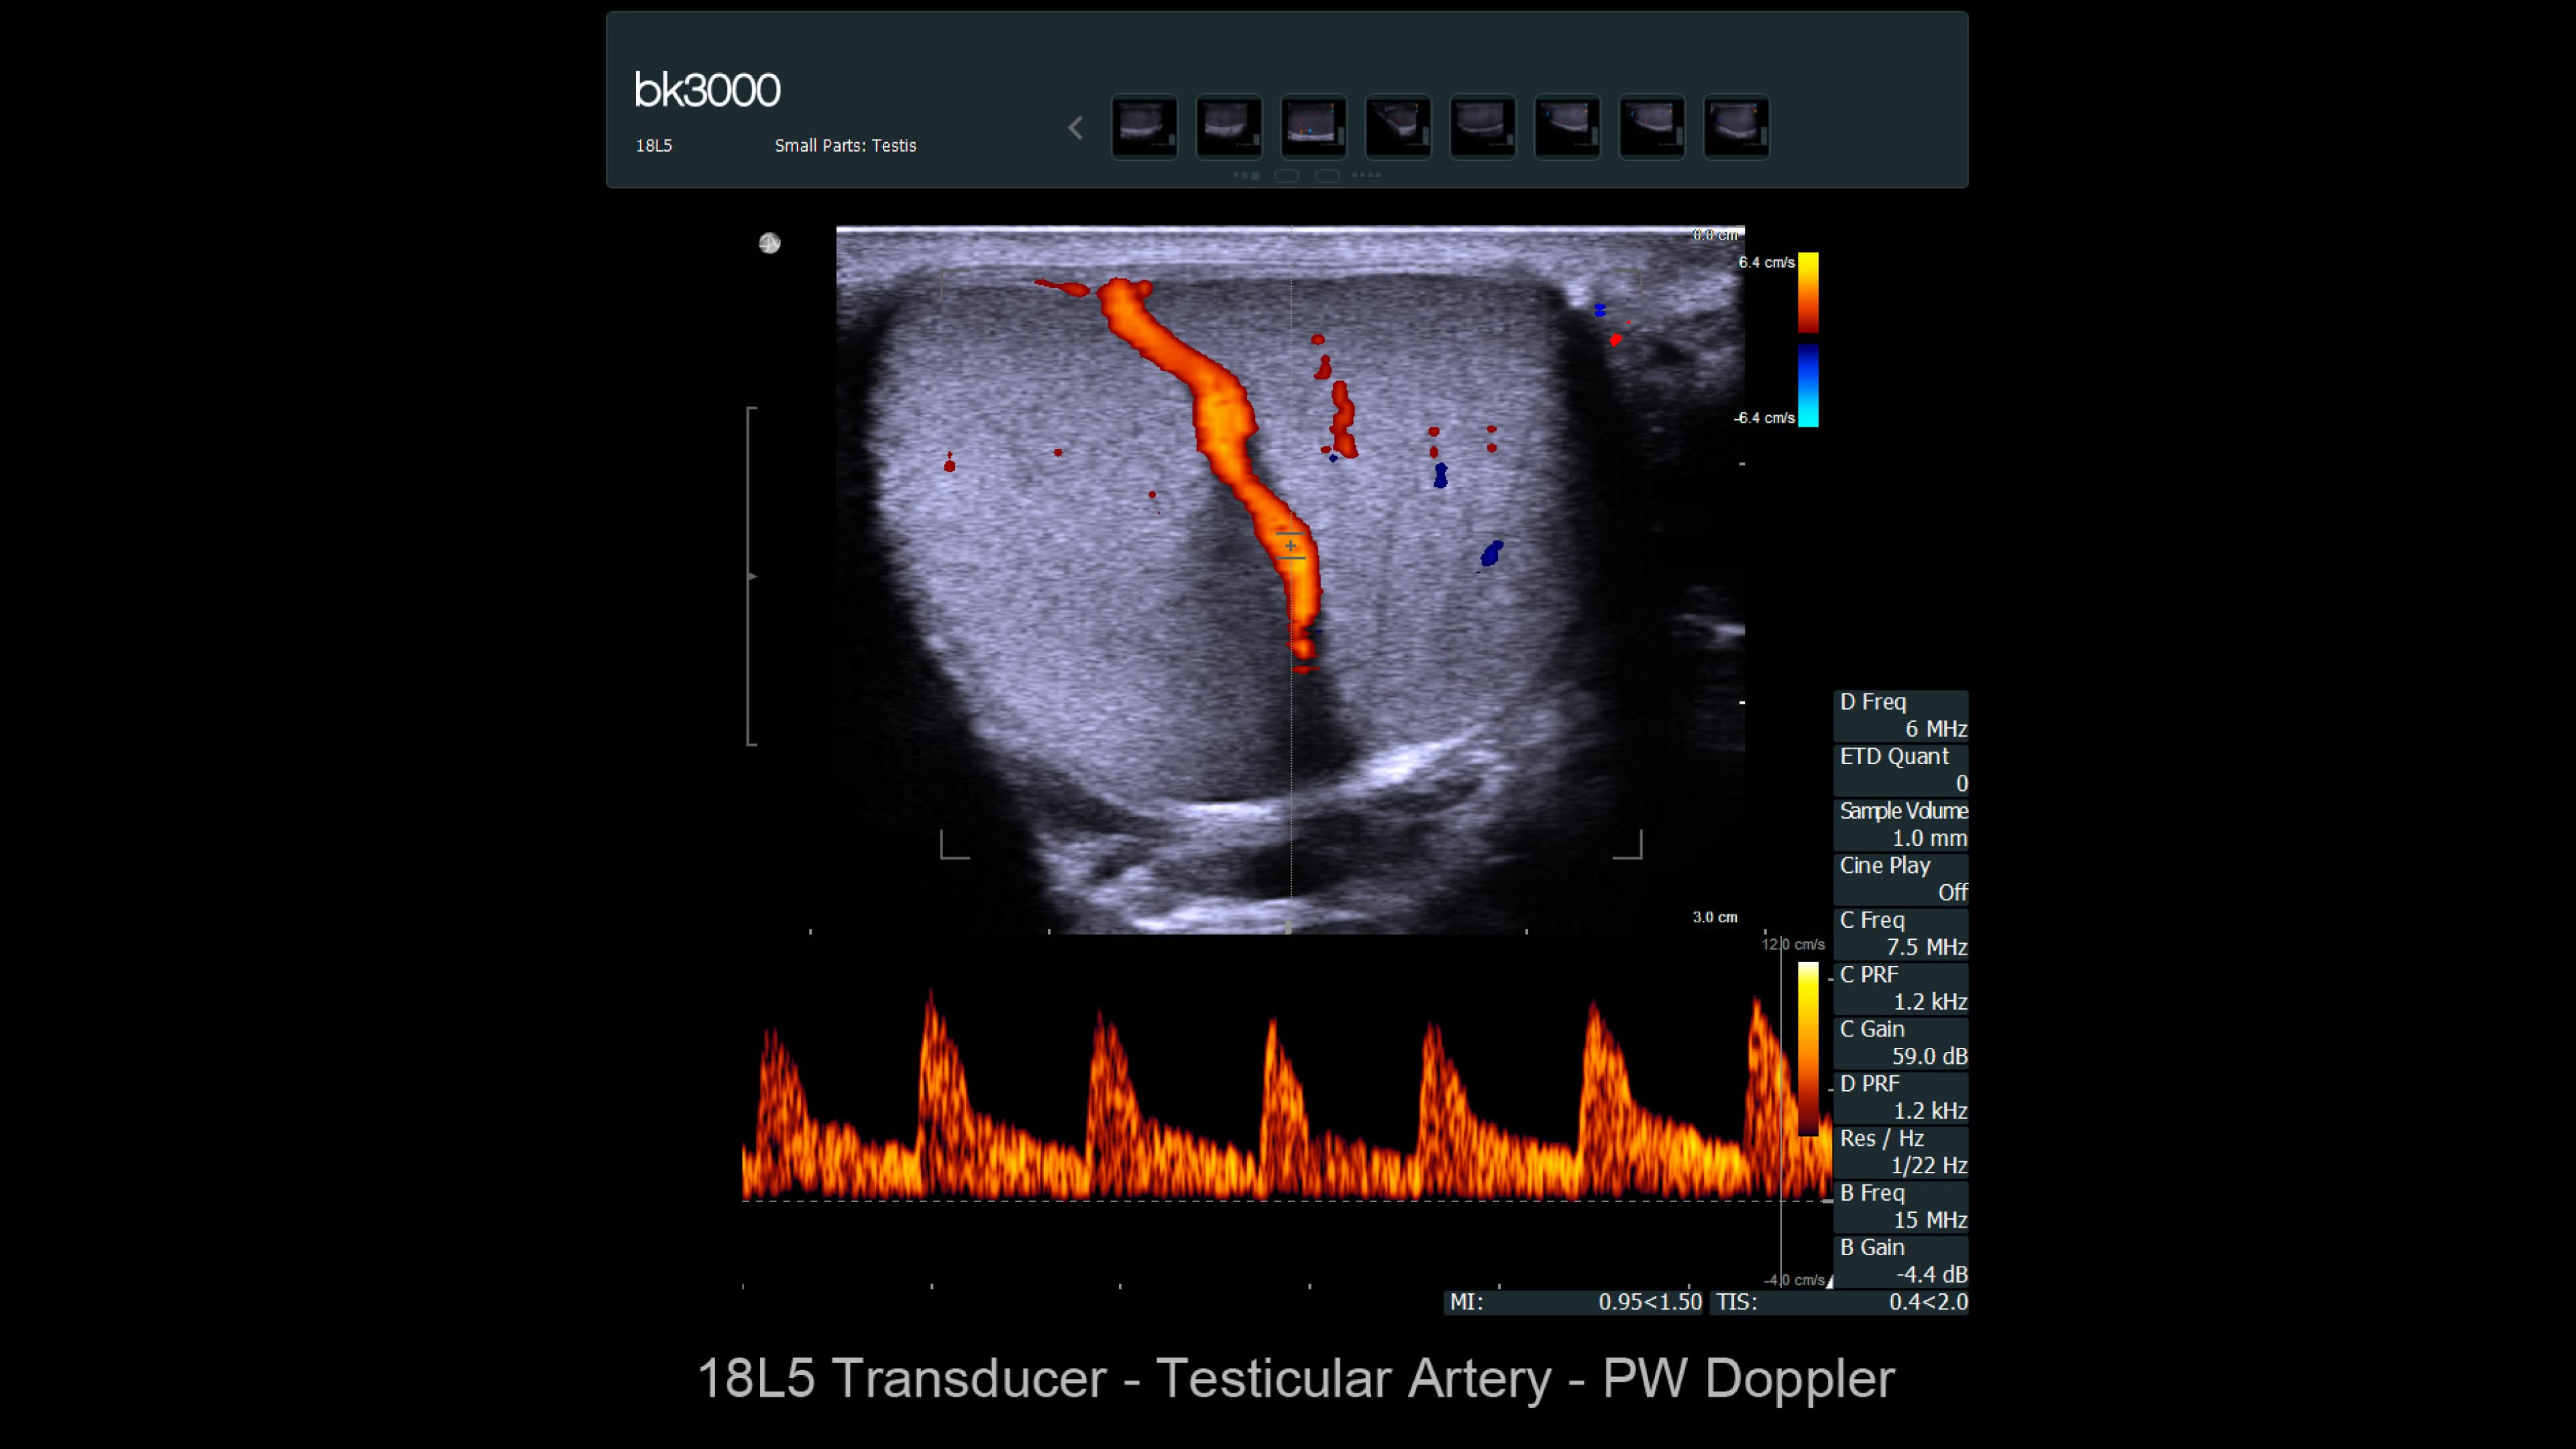

Ultrasound provides detailed information for kidney imaging, measurement, and biopsies. The bk3000 and bkSpecto systems help visualize fine anatomical details, see vascularization, measure blood flow, and locate kidney stones. The bkActiv, our flagship system, offers next-level imaging for prostate, renal, kidney, and bladder imaging, with sensitive Doppler for blood flow. Combined with sterilizable transducers, the bkActiv sets a new standard for surgical urology.

bk3000 ultrasound system

Discover the bk3000 ultrasound: high-resolution imaging for urology, colorectal, and pelvic floor care with advanced 3D and triplane precision.